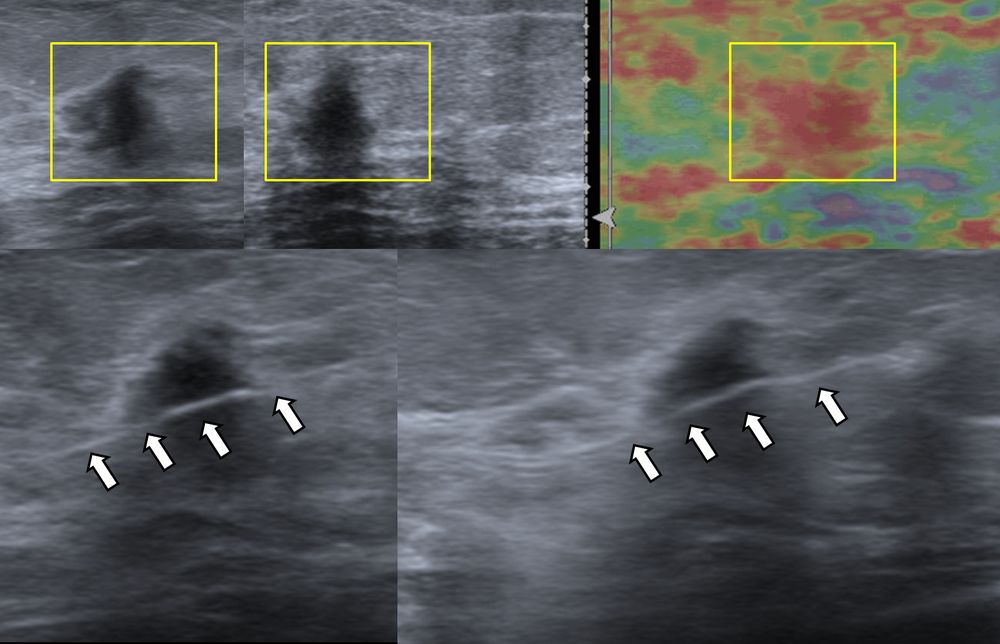

- Υπερηχογραφικά καθοδηγούμενη βιοψία μαστού - core biopsy

Εχει αντικαταστήσει την FNA στις συμπαγείς βλάβες του μαστού, γιατί η ποσότητα του ιστού που συλλέγεται είναι μεγαλύτερη και το αποτέλεσμα πιο αξιόπιστο.